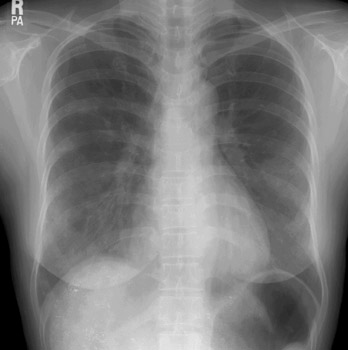

患者女性,43岁,肝癌tace治疗后出现胸闷不适.

请分析肺部改变的成因及可能的诊断.

动静脉瘘,栓塞剂经瘘口进入肝静脉--下腔静脉--右心房--右心室--肺动脉--沉积于肺内.

原发性肝癌进行栓塞治疗时,若肝动脉造影显示肿瘤侵犯肝静脉,且有明显的肝动静脉瘘,则使用碘油乳剂就不妥当,因为大量碘油可通过瘘道进入肺部,引起肺栓塞的并发症。